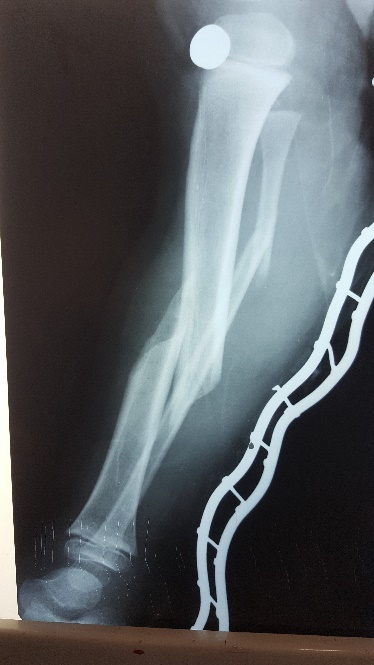

Այս ուսումնասիրությունը հիմնված է 21 հիվանդների (17 տղա, 4 աղջիկ) շարունակական խմբի բուժման արդյունքների վերլուծության վրա, որոնք ենթարկվել են տիտանե էլաստիկ մեխերով վիրահատության։ Հիվանդների տարիքը եղել է 4 տարեկանից մինչև 16 տարեկան։ 9 երեխայի մոտ կոտրվածքի պատճառ է հանդիսացել ձեռքի վրա անկումը, մնացածի մոտ կոտրվածքն առաջացել է վերջույթի ոլորման արդյունքում, վնասվածքի մեխանիզմը եղել է ուղիղ: 19 դեպքերում կոտրվածքները եղել են փակ, իսկ 2 դեպքում՝ բաց։ Ըստ վնասվածքի տեղայնացման՝ դրանք եղել են դիաֆիզար կոտրվածքներ (15 դեպք), պրոքսիմալ մետաֆիզի մակարդակի կոտրվածք (3 դեպք) և հեռավոր մետաֆիզի՝ (3 դեպք): Կոտրվածքային գծի բնույթի համաձայն՝ դիաֆիզային կոտրվածքներից հայտնաբերվել են 6 լայնակի, 4 թեք, 5 պտուտակաձև։ Մի տղայի մոտ (4 տարեկան), որի մոտ առկա էր սրունքի մ/3-ի բաց թեք կոտրվածք տեղաշարժով և մաշկի մինուս հյուսվածքներով, կատարվել է նաև վերքերի առաջնային վիրաբուժական մշակում և կարում՝ ռետինյա արտաթորիչներով։ Սակայն մի քանի շաբաթ անց սկսվել է մաշկի նեկրոզ։ Այդ իսկ կապակցությամբ կատարվել է երկրորդ վիրահատական միջամտությունը։ Կատարվել է մաշկի աուտոտրանսպլանտացիա։ Մաշկի կտորները վերցվել են առողջ ազդրի առաջային մակերեսից: (Նկ 1)